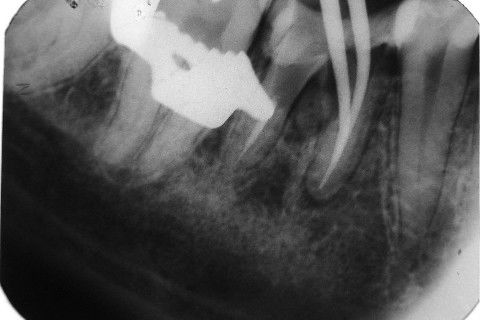

Retratamento de Canal, Tratamento de Perfuração, Restauração Provisória com Resina, Núcleo e Provisório.

RETRATAMENTO DE CANAL, TRATAMENTO DE PERFURAÇÃO, RESTAURAÇÃO PROVISÓRIA COM RESINA, NUCLEO E PROVISÓRIO.